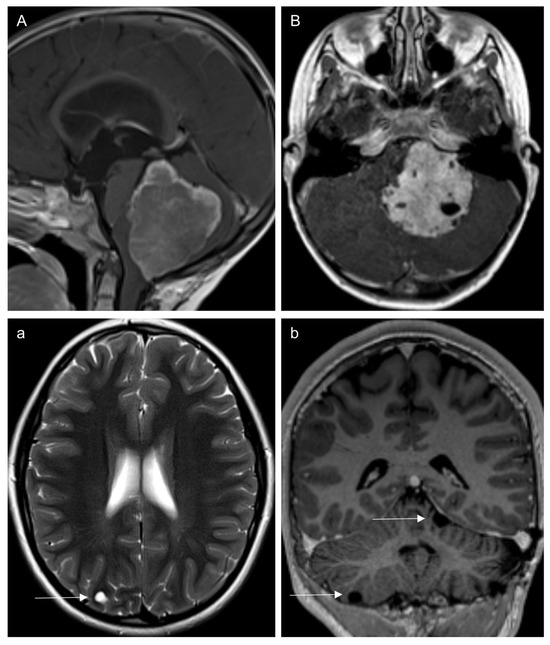

3.3. Leptomeningeal Dissemination (Table 2)

3.3.1. At Diagnosis

3.3.2. On Follow-Up